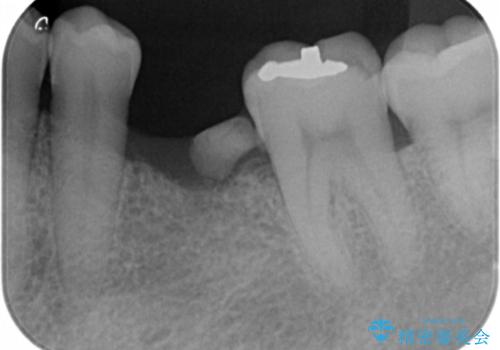

奥歯の欠損 インプラント治療

- 奥歯を失ったのち放置してしまった部位にインプラント治療を希望されて来院されました。

少量の骨造成を併用したインプラント治療を計画します。